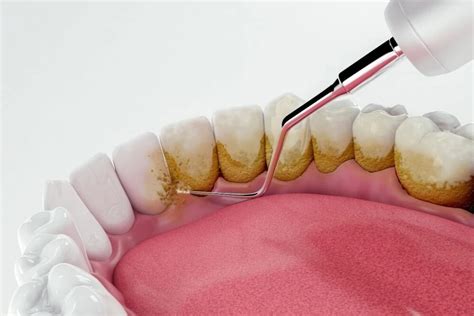

Tartrectomía: El Procedimiento Clave

La tartrectomía es un procedimiento odontológico que consiste en la eliminación profesional del cálculo dental (sarro) y otros depósitos mineralizados adheridos a la superficie de los dientes. En términos sencillos, es la limpieza dental que realiza el dentista o higienista para remover la placa bacteriana calcificada que no puede quitarse con el cepillado normal.

La tartrectomía se realiza mediante dos tipos básicos de instrumental periodontal: instrumental manual y ultrasonidos.

- Instrumental Manual: Incluye herramientas de acero especialmente diseñadas, como las curetas (ej. curetas Gracey o universales) y los escarificadores de hoz, que poseen bordes cortantes para raspar el sarro de las superficies dentarias.

- Instrumentación Mecánica: Emplea aparatos de ultrasonido o sónicos (aire) que vibran a alta frecuencia. Estos dispositivos cuentan con puntas metálicas intercambiables de diferentes formas adaptadas a distintas áreas dentales.

La combinación de ultrasonidos y herramientas manuales es habitual: el ultrasonido rompe y desprende la mayor parte del cálculo, y luego las curetas manuales eliminan residuos remanentes y pulen las superficies dentales donde el aparato ultrasónico no alcanzó.